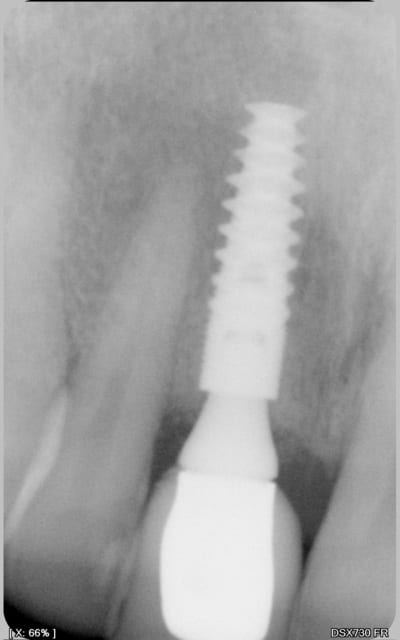

Il s'agit d'une EIIMCI avec comblement du gap.

J'ai utilisé un pilier plein que je n'ai pas déposé depuis la chirurgie.

Avec une provisoire transvissée, tu as un risque de contamination du joint pilier-implant par le sulcus le long du pilier et par le puits de transvissage. Et les procédures prothétiques nécessitent le dévissage revissage a plusieurs reprises.

Là, la contamination de cet espace est uniquement possible au travers de l'attache épithélialo-conjonctive. Et comme le pilier est vissé le jour de la pose et n'est plus démonté par la suite, je pense que cette attache peut mieux résister.

Pilier titane nitruré + coiffe zircone, mais quand je parle de biologique je fais références au meilleures conditions possibles pour protéger la greffe pendant la cicatrisation.